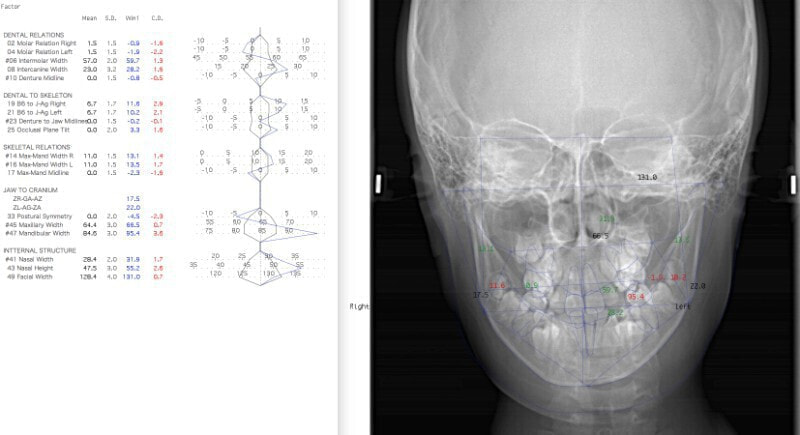

最診断時のセファロ分析:

下顎前突症例によくある顕著な顔面非対称もなく、幅径も良好な状態です。

少し大臼歯の傾斜が認められます。

上顎8番は先天欠如、下顎8番は埋伏しております。

歯根のパラレリング(平行性)も悪くなく、上顎洞、顎関節にも異常所見はありません。